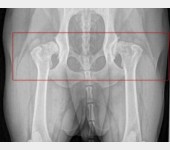

Mój ukochany Max ma dysplazje stawów tylne nogi oraz biodra odmawiają posłuszeństwa. Dotychczas starałam się finansować każdą wizytę, operację, zabiegi i rehabilitację. Niestety, nadszedł moment, gdy zostałam postawiona pod ścianą. Z osoby wspomagającej, mój przyjaciel i ja staliśmy się potrzebującymi.

Niestety stopień zwyrodnienia stawów i poziom zaawansowania choroby kwalifikuje Maxa na operację wstawienia endoprotez w obu biodrach, których koszt mimo moich oszczędności przekracza moje możliwości